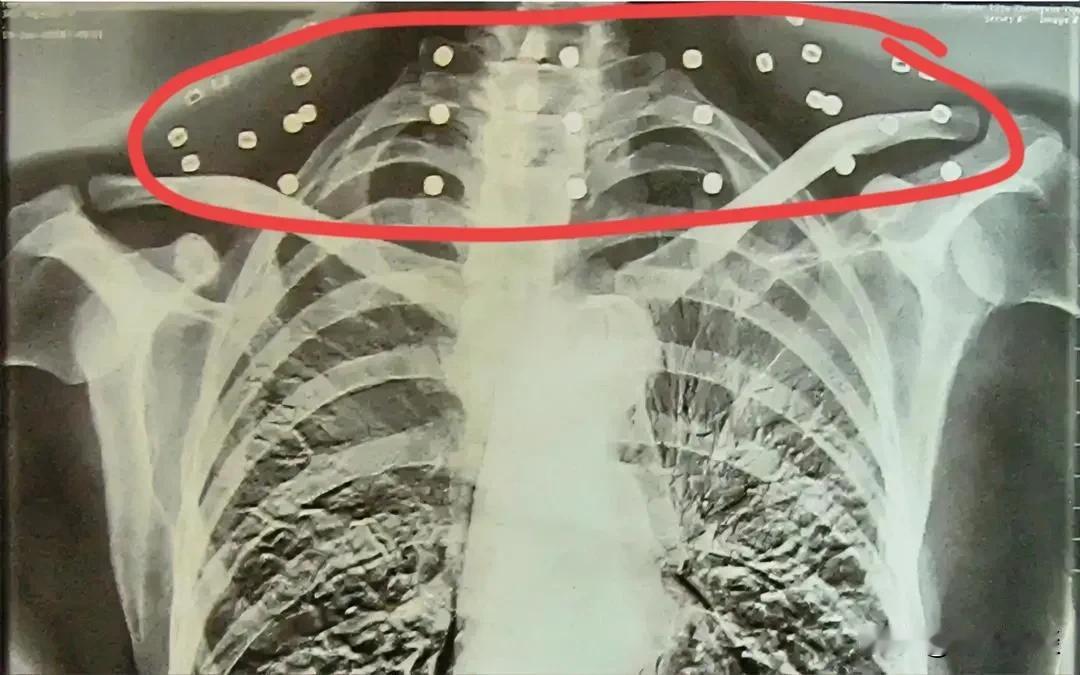

看完泪奔!特殊的“项链”,永远的勋章! 大家看了没,一老人去做检查,被医生提醒要取下项链才能拍片,可老人说“我从来没有戴过项链”,天啊,是弹片,是敌人的弹片,一“戴”就是几十年,可想而知,这老人忍受过无法想象的剧痛,或许长期忍受着痛已经痛到感觉不到体内有异物的存在了…敬佩! 特殊的“项链”,致敬英雄!